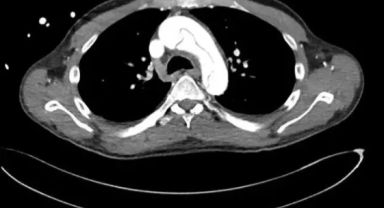

59 Yaşındaki Adam Mastürbasyon Sırasında Aort Damarı Yırttı: İlginç ve Tehlikeli Bir Vaka